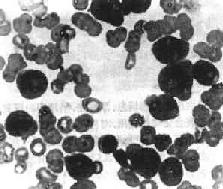

一、急性白血病急性白血病起病急,常表现为发热、乏力、进行性贫血、出血倾向、淋巴结及肝、脾肿大等。 急性白血病时造血干细胞或原始和幼稚的白细胞恶变,发生分化障碍,不能分化为成熟的细胞,使骨髓内原始和幼稚细胞大量堆积,成熟的细胞明显减少。大量异常的原始和幼稚幼胞增生,抑制正常的造血干细胞和血细胞生成,引起红细胞、白细胞和血小板减少。多能造血干细胞分化过程中的任何阶段都可能发生恶变转化为白血病细胞。根据累及的细胞类型可分为急性淋巴细胞性白血病(ALL)和急性粒细胞性白血病(AML)。 (一)急性淋巴细胞性白血病 本病多见于儿童和青年人。根据形态学和免疫学特点可分为不同的亚型。 1.国际上通用的法、美、英协作组的FAB分类,根据瘤细胞形态将急性淋巴细胞性白血病分为L1,L2,和L3型。 L1型:细胞较小,大小一致。核较大,圆形,染色质均匀、细致,核仁不明显。胞浆少,嗜碱性。这种类型多见于儿童。 L2型:细胞较大,约为正常成熟小淋巴细胞的2倍。细胞大小不一,胞浆丰富,嗜碱性。细胞核形状不规则,有些有裂隙或切迹或呈折叠状,常有1~2个明显的核仁。这种类型多见于成人或大年龄儿童。 L3型:细胞大,大小一致。胞浆丰富,嗜碱性,胞浆内常有小空泡。细胞核圆或椭圆形,外形规则。染色质致密、均匀,呈点彩状,常有一个或多个明显的核仁。 2.免疫学分类 应用免疫标记和TCR及Ig基因重组技术,根据白血病细胞的来源和分化的不同阶段分类。免疫学分类与预后有关,有助于指导临床治疗。 (1)B细胞性ALL(B-ALL):ALL中约80%来源于B细胞。可分为3种亚型,其中2种来自原始B细胞。①前B细胞ALL,约占ALL的60%。来自早期的原始B细胞,CD19+,CD10+,预后最好;②前B细胞ALL,约占ALL的20%,CD19+,CD10+,CD20+,Cμ+,预后较好;③较成熟的B细胞ALL很少见,约占ALL的1%~2%,除CD19+,CD20+外SIg+,预后最差。 (2)T细胞性ALL(T-ALL):约占ALL的15%,来自原始T细胞,CD2+,CD7+,CD5+,预后较差。 (3)无标记(未分类)ALL:在ALL中<5%,没有B细胞和T细胞标记,预后较差。 (二)急性粒细胞性白血病 多见于成人,儿童较少。多能髓细胞样干细胞在分化过程的不同阶段都可发生恶变,因此AML的细胞来源不同,可分为多种类型。FAB分类根据白血病细胞分化的程度和主要的细胞类型分为M1至M7七个类型。 M1 急性原粒细胞白血病未分化型大多数瘤细胞为原粒细胞,少数为早幼粒细胞。 M2 急性原粒细胞白血病分化型瘤细胞包括多数原始粒细胞和多数早幼粒细胞及多少不一的中幼粒以下的细胞。 M3 急性早幼粒细胞白血病以早幼粒细胞为主,胞浆内充满髓过氧化物酶阳性颗粒。 M4 急性粒-单核细胞白血病瘤细胞包括粒细胞及单核细胞两种方向分化。粒细胞同M2,但同时有多数幼单核细胞和单核细胞。 M5 急性单核细胞白血病以原单核细胞为主或以幼单核细胞为主。 M6 急性红白血病瘤细胞以畸形、多核或分叶状核的原红细胞为主,同时有原单核细胞和早幼单核细胞。 M7 急性巨核细胞白血病主要为多形性、未分化的原巨核细胞。 【病理变化】 白血病的特点是骨髓内异常白细胞大量增生,进入周围血并可浸润肝、脾、淋巴结等全身各组织和器官。增生的白血病细胞形态与其来源的相应正常细胞相似,但分化不成熟,有一定的异型性。各种白血病类型虽然不同,但引起的病变有许多共同之处,包括大量白血病细胞增生直接引起的病变和白血病细胞浸润各组织、器官引起的继发性病变。 1.周围血像早期即出现贫血,白细胞总数多少不等,白细胞增多性与不增多性者约各占一半。白细胞增多性者,白细胞总数多在2万~5万/μl,常呈进行性上升,可高达10至数10万。其中有大量原始和幼稚细胞(图11-6)。白细胞不增多性白血病的白细胞计数可正常或减少,有时可降低至1000~3000/μ1,较难找到原始或幼稚细胞。血小板减少有时达1万/μ1以下。

图11-6 急性粒细胞性白血病 周围血内有大量原始粒细胞 2.骨髓骨髓内白血病细胞大量增生,可取代正常骨髓组织,并可侵蚀骨松质和骨皮质。病变以椎骨、胸骨、肋骨和盆骨最显著,严重者可侵犯长骨。急性白血病的骨髓增生极为活跃,其中主要为原始细胞,较成熟的白细胞不多,幼稚红细胞和巨核细胞生成受抑制,数量减少。有些急性粒细胞白血病时大量瘤细胞主要为原粒细胞,在骨组织、骨膜下或软组织中浸润,可聚集形成肿块,称为绿色瘤(chloroma),多见于颅骨和眼眶周围。瘤细胞浸润之处呈绿色,暴露于空气中后,绿色迅速消退。用还原剂(过氧化氢或亚硫酸钠)可使绿色重现。绿色色素的性质还不肯定,有人认为其中含有原卟啉、胆绿蛋白或绿色过氧化物酶,可能与瘤细胞的异常代谢产物有关。 3.淋巴结 全身淋巴结都可有不同程度的肿大,以儿童ALL时较多见,也最明显,AML时较轻。肿大的淋巴结一般不互相粘连,有弹性。切面呈均匀的灰白色。镜下可见淋巴结内有大量瘤细胞浸润。淋巴结结构可部分或全部被破坏。瘤细胞可侵犯淋巴结包膜及包膜外脂肪组织。AML时淋巴结内瘤细胞浸润较少,部分淋巴结结构可保留。 4.脾 急性白血病时脾轻度至中度肿大。儿童ALL时脾肿大较多见,也较明显。成人AML时多轻度肿大。肉眼观,肿大的脾包膜紧张,呈暗红色,质软。镜下,ALL时红髓和血窦内有大量白血病细胞浸润,可形成结节状。脾小体可增大或消失。AML时,主要累及红髓,原粒细胞增生,可压迫脾小体,严重时红髓和脾小体结构可被破坏。 5.肝 肝中度增大,表面光滑。镜下,AML时瘤细胞主要沿肝窦在肝小叶内弥漫浸润。ALL时瘤细胞主要浸润于汇管区及其周围的肝窦内。单核细胞性白血病较少累及肝,其浸润方式与粒细胞白血病相似。 除上述器官外,急性白血病时白血病细胞还常浸润脑、脊髓、周围神经、心肌、肾、肾上腺、甲状腺、睾丸和皮肤等乃至全身各器官和组织。瘤细胞多首先出现在血管周围,逐渐向邻近组织浸润,可引起出血并可压迫和破坏邻近组织。 白血病的皮肤病多见于急性单核细胞白血病(M5)。病变多样,可局限于一处也可播散到身体大部,形成各种扁平或隆起的斑块或丘疹。瘤细胞多浸润于真皮内,一般不侵犯表皮。有时单核细胞白血病可浸润牙龈,使牙龈粘膜肿胀肥厚,常有出血,并可形成表浅溃疡,易引起继发感染。 6.继发性变化由于白血病细胞广泛浸润,常破坏相应的组织或器官,引起一系列继发性改变: (1)出血:白血病细胞浸润骨髓组织,引起贫血和血小板减少,故常易出血。皮肤可有出血点和瘀斑。牙龈、肾盂、肾盏和膀胱粘膜、浆膜都可有出血灶,有时脑组织出血可形成血肿。 (2)感染:白血病时虽然白细胞大量增生但无抗病功能。患者免疫功能和抵抗力低下,常并发细菌和真菌感染,常见的有白色念珠菌、曲菌和毛霉菌感染等,成为白血病常见的致死原因。 急性白血病病情急,预后差,早期即出现贫血、出血和继发性感染,死亡率很高。近年来由于联合化疗的应用,对提高急性白血病的缓解率,延长生存期都取得了良好的效果。尤其是儿童ALL可长期缓解。